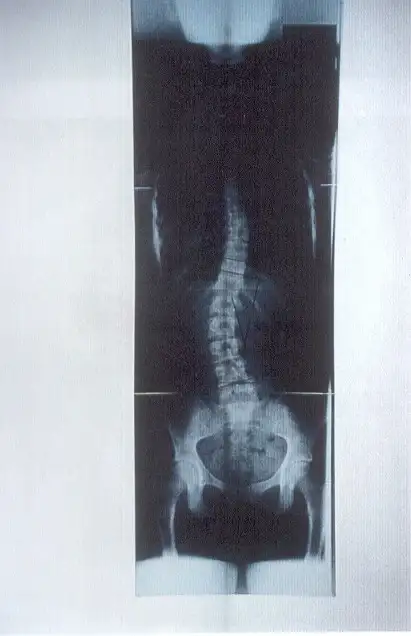

Điều trị vẹo cột sống

Có nhiều nguyên nhân khác nhau dẫn đến vẹo cột sống, bao gồm di chứng của bại liệt, bại não, tật nứt đốt sống, dị tật đốt sống và chấn thương hệ thần kinh-cơ-xương, nhưng trong phần lớn các trường hợp, không xác định được nguyên nhân cụ thể. Trường hợp này được gọi là vẹo cột sống vô căn (nghĩa là không rõ nguyên nhân).

Vẹo cột sống vô căn (Idiopatic Scoliosis): là tình trạng cột sống bị cong, vẹo mà không rõ nguyên nhân Đây là dạng thường gặp nhất trong các loại vẹo cột sống có cấu trúc cố định (tức là cột sống cong thật, không phải do tư thế). Bệnh thường bắt đầu ở trẻ em hoặc thanh thiếu niên và có thể nặng dần lên cho đến khi cơ thể ngừng phát triển xương (khoảng sau tuổi dậy thì). (Stagnara, 1988.)

Việc đeo Áo chỉnh hình (orthosis) thường có thể điều trị vẹo cột sống, tuy nhiên nếu góc cong của cột sống vượt quá 45º thì sẽ rất khó điều trị bằng phương pháp này. (Thomas M. Gavin và cộng sự, 2001)

Điều trị bằng nẹp chỉnh hình được khuyến nghị cho những bệnh nhân chưa trưởng thành về mặt xương khớp và có độ cong tiến triển từ 25º đến 45º (theo góc Cobb), trong khi phẫu thuật cố định cột sống được chỉ định cho các trường hợp có độ cong vượt quá 45º. (Thomas M. Gavin và cộng sự, 2001)